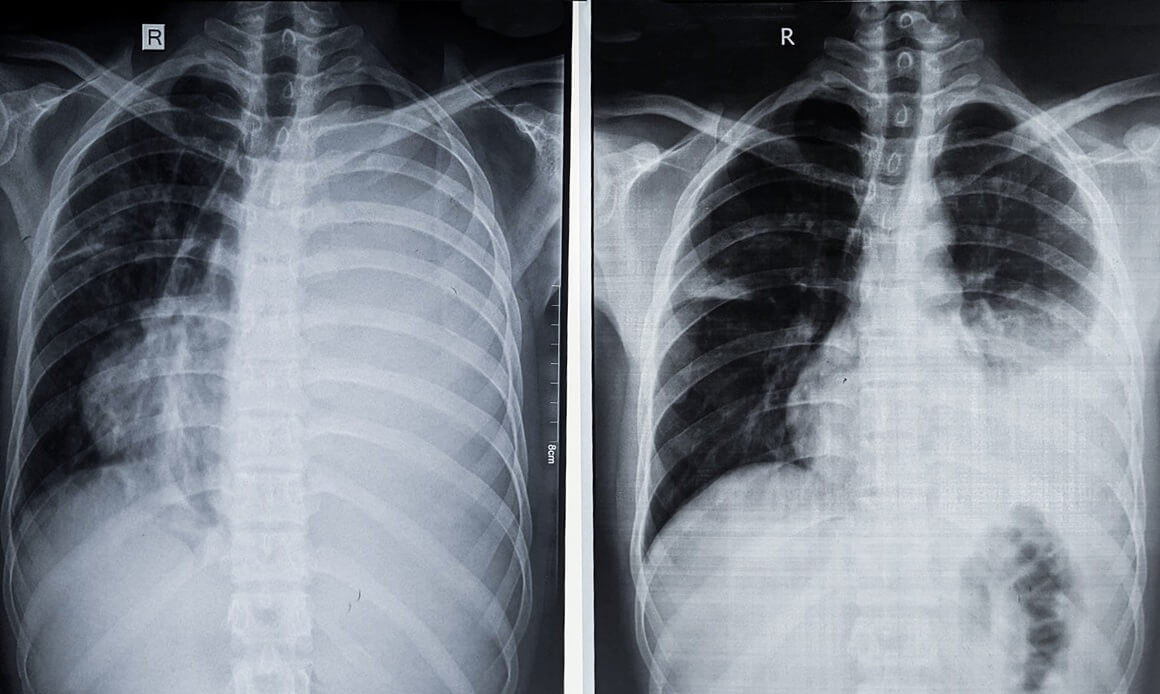

- pregled pluća X-zrakama, odnosno rendgen pluća – može učinkovito dokazati prisutnost tekućine u pleuralnom prostoru koja se pojavljuje kao bjelkasta mrlja u dnu pluća